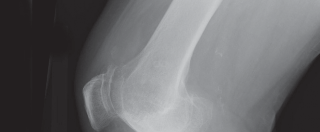

High-quality, standardized, weight-bearing radiographs are the cornerstone of preoperative planning. A standard knee series must include a weight-bearing anteroposterior (AP) view, a weight-bearing lateral view in extension, and a skyline (Merchant) view of the patella. The AP view reveals joint space narrowing, subchondral sclerosis, osteophyte formation, and the presence of subchondral cysts. The lateral view is essential for assessing patellar height (Insall-Salvati ratio) and the posterior slope of the tibia.

Crucially, we must obtain a 45-degree posteroanterior (PA) weight-bearing view (the Rosenberg view). Because cartilage wear in early-to-moderate OA predominantly affects the posterior aspect of the femoral condyles, the standard extension AP view may falsely appear normal. The flexed Rosenberg view unloads the patella and brings the worn posterior condyles into contact with the tibia, revealing hidden joint space narrowing. Furthermore, a full-length, hip-to-ankle standing radiograph is highly recommended, particularly in patients with severe deformities or a history of prior femoral/tibial fractures, to accurately determine the mechanical axis and identify any extra-articular deformities that might complicate intramedullary instrumentation.